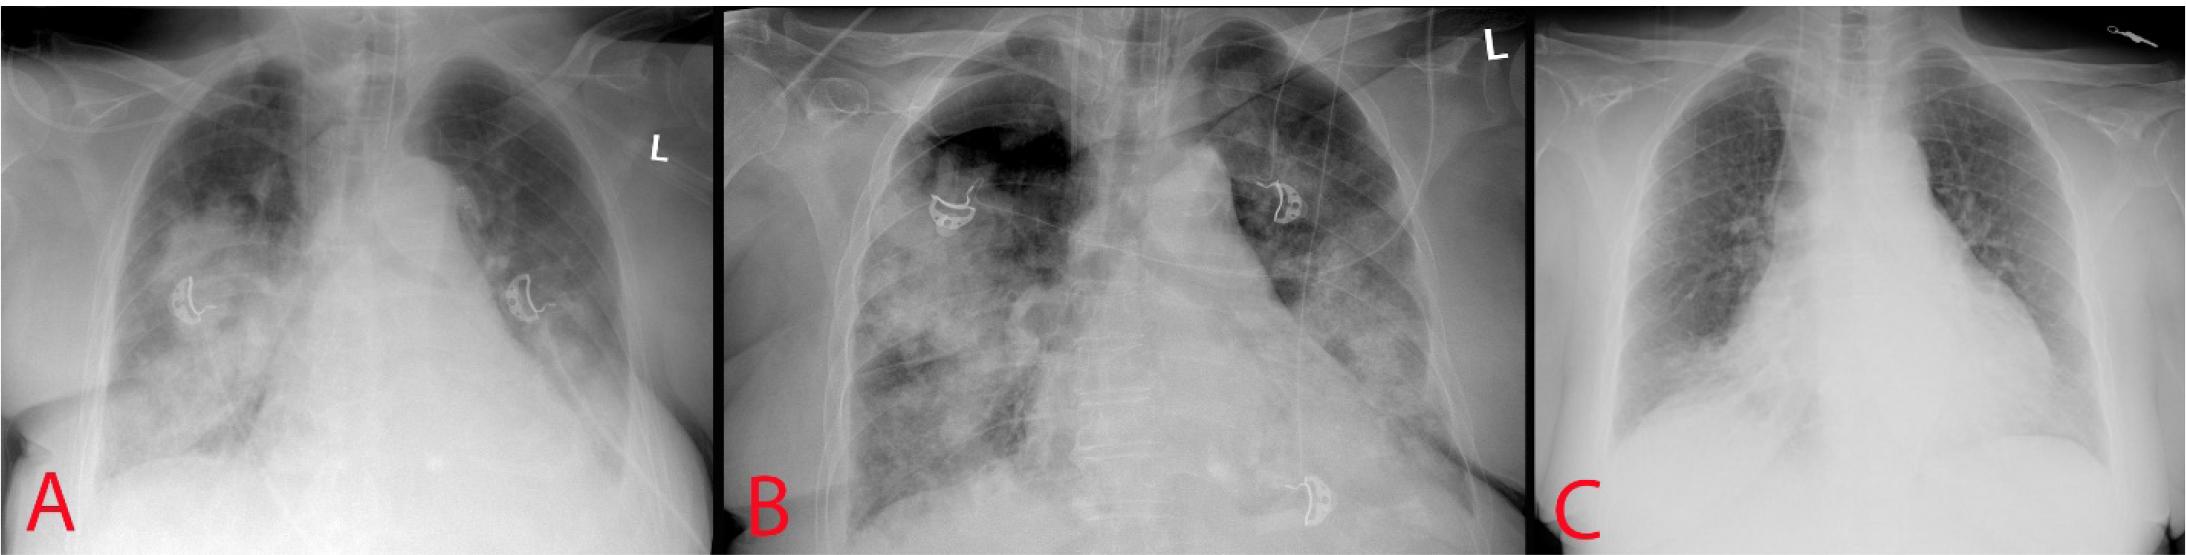

The chest X-ray showed bilateral opacification of the lung field consistent with pulmonary edema (Figure 1). Echocardiography revealed a mass in the left ventricle. Figure 2 shows a hyperechoic mass of an irregular round shape with clear, uneven contours and a pronounced acoustic shadow. The mass is fixed to the posterior leaflet of the mitral valve and partially to the basal segment of the lateral wall; however, a reliable assessment of its position in transthoracic echocardiogram is difficult. Left atrium (LA) width was 40 mm (normal range [RN] = 27-38 mm). LA volume was 48 ml (NR = less than 52 ml). In the left atrium there was a hypoechogenic mass with an area of 20 × 18 mm. Left ventricle end-systolic volume (ESV) was 22 ml (NR = less than 24 ml), end-dyastolic volume (EDV) was 57 ml (NR = less than 61 ml). Ejection fraction (biplane Simpson) was 50%. Contractile function of the left ventricle in basal, mid and apical segments was normal. Interventricular septum width in inferolateral segment was 12 mm, which confirms the presence of slight hypertrophy. Left ventricular posterior wall was 8 mm. Right atrium (RA) width was 25 mm (NR less than 29 mm). RA square was 17 mm2 (NR was less than 18 mm2).

Chest X-Ray. A – at admission; B – 2nd day of admission; C – at the time of discharge.